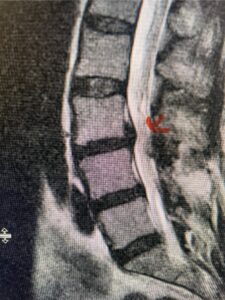

Figs. 1a: Sagittal lumbar T2-weighted MRI demonstrating severe lumbar stenosis with a slight grade 1 at L3-4 and a disc protrusion (red arrow )

Fig 4: Sagittal T2-weighted lumbar MRI demonstrating an L4-5 grade 1 spondylolisthesis with obvious emanation of the disc herniation from the L4-5 level (red arrow)